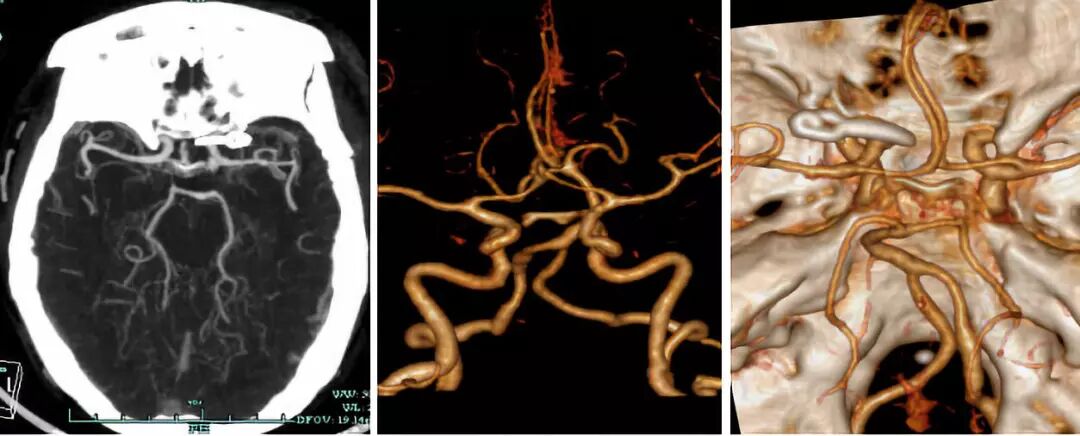

1. 术前CTA: